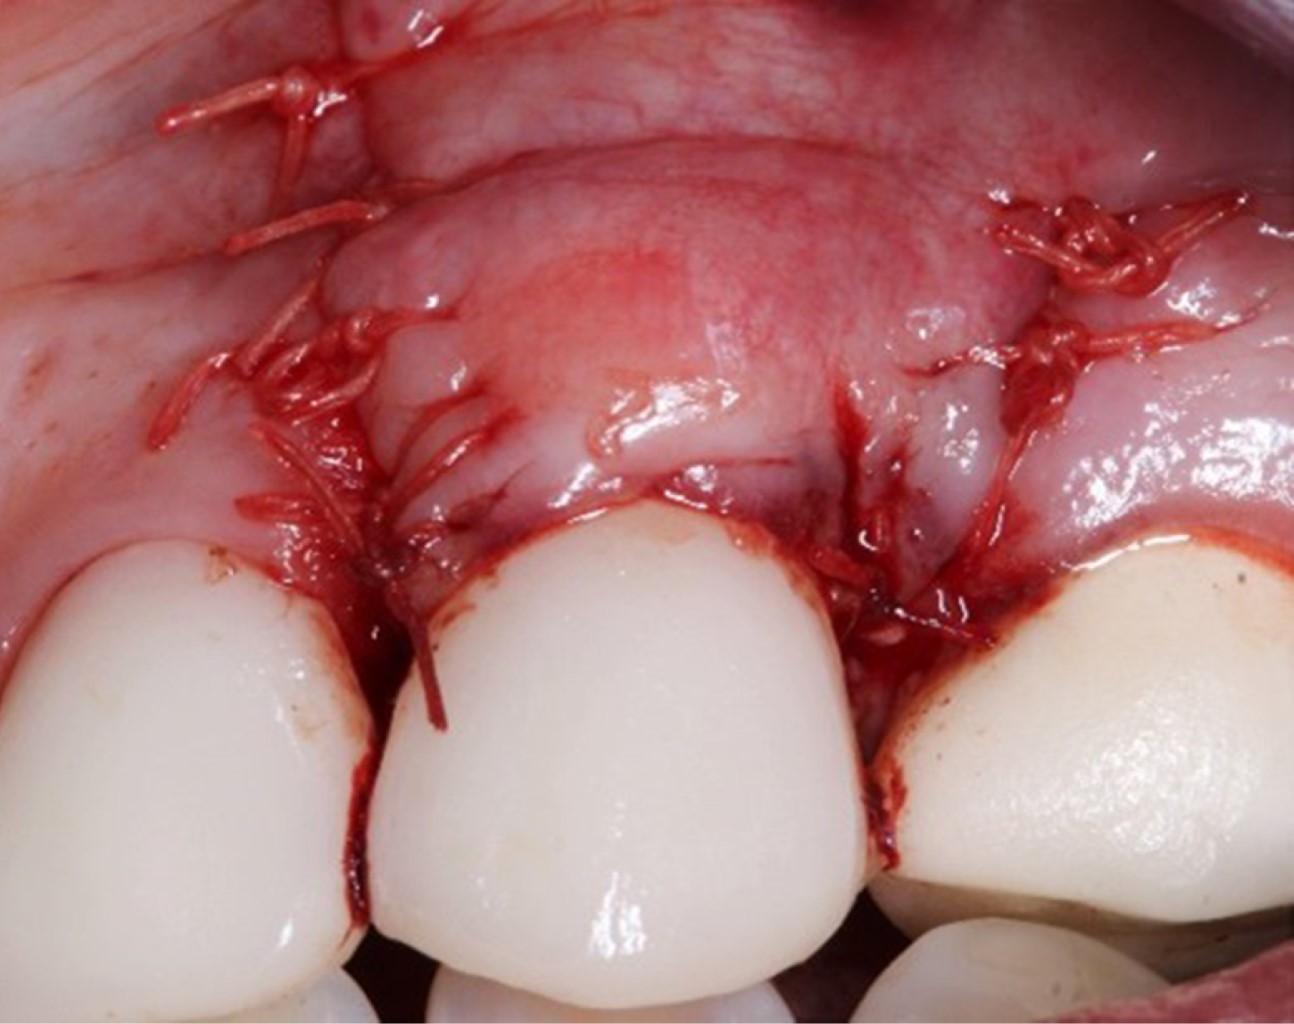

Se realizó la preparación del sitio receptor mediante incisiones oblicuas con bisturí Bard Parker® #3 y hoja de bisturí #15c a nivel de la unión cemento-esmalte en la base de cada papila adyacente, seguido de dos liberatrices oblicuas y una incisión intrasulcular, la cual unía las dos liberatrices. Posteriormente, se realizó la elevación del colgajo de espesor parcial a nivel lateral de las recesiones, elevación de colgajo a espesor total apical a la recesión gingival, continuado hasta la unión mucogingival, donde se realizó una incisión horizontal sobre el periostio para lograr la desinserción y liberación mucosa del colgajo (Figura 3).

Las papilas anatómicas fueron desepitelizadas con tijeras LaGrange S14® (Figura 4). Luego de la preparación del sitio receptor, se tomaron las medidas del sitio para la obtención del injerto de tejido conectivo, obtenido de la región palatina (sitio donador) mediante cuatro incisiones, al menos 2 mm apicales de distancia del margen gingival de los premolares. De esta forma se obtuvo un injerto libre de tejido conectivo epitelizado, de 10 mm de largo por 4 mm de ancho y 2 mm de grosor (Figura 5). Se eliminó el epitelio de manera extraoral, mediante hojas de bisturí #15.

El injerto fue adaptado en el sitio receptor a nivel de la unión cemento-esmalte, el cual fue suturado mediante puntos simples, con sutura de ácido poliglicólico (PGA) (Vicryl®) 5-0 (Figura 6).

El colgajo preparado previamente se reposicionó y suturó a 2 mm en dirección coronal a la unión cemento-esmalte, mediante sutura suspensoria. Se realizaron suturas simples complementarias en las liberatrices oblicuas (Figura 7). El sitio donador se suturó con una sutura suspensoria en "8" de ácido poliglicólico PGA (Vicryl®) 5-0.

Figura 7

Figura 8